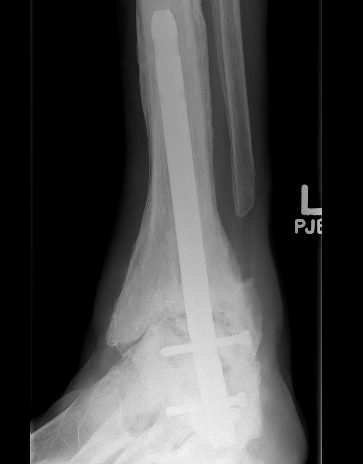

B. Lateral approach and fibular osteotomy

Zimmer Biomet Trabecular Metal PDF

Vumedi fibula osteotomy approach for total ankle arthroplasty